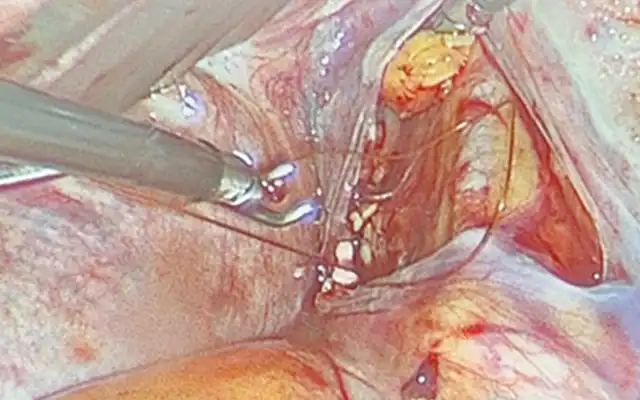

Laparoscopic Excision of Cesarean Scar Pregnancy and Repair of the Uterine Defect (Video Article)

Laparoscopic Excision of Cesarean Scar Pregnancy and Repair of the Uterine Defect (Video Article)2025-12-18T13:19:35+00:00